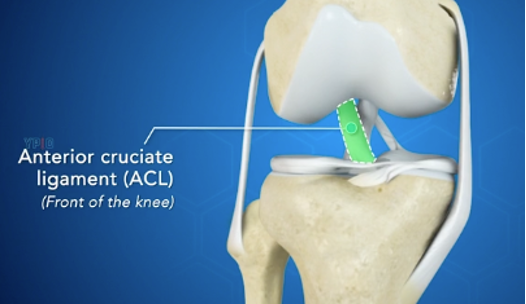

Elülső keresztszalag (ACL):

Az elülső keresztszalag (ACL) a térd egyik fő stabilizáló szalagja. Az ACL a térd ízület központjában található és a combcsontot köti össze a sípcsonttal.

Az ACL megakadályozza, hogy a combcsont hátrafelé csússzon a sípcsonton (vagy a sípcsont előrefele csússzon a combcsonthoz képest).

Együtt a hátsó keresztszalagal (PCL), az ACL a térd stabilizátora a forgó mozgások tekintetében is. Ha az egyik ilyen szalag jelentősen károsodik, a térd instabil lesz.